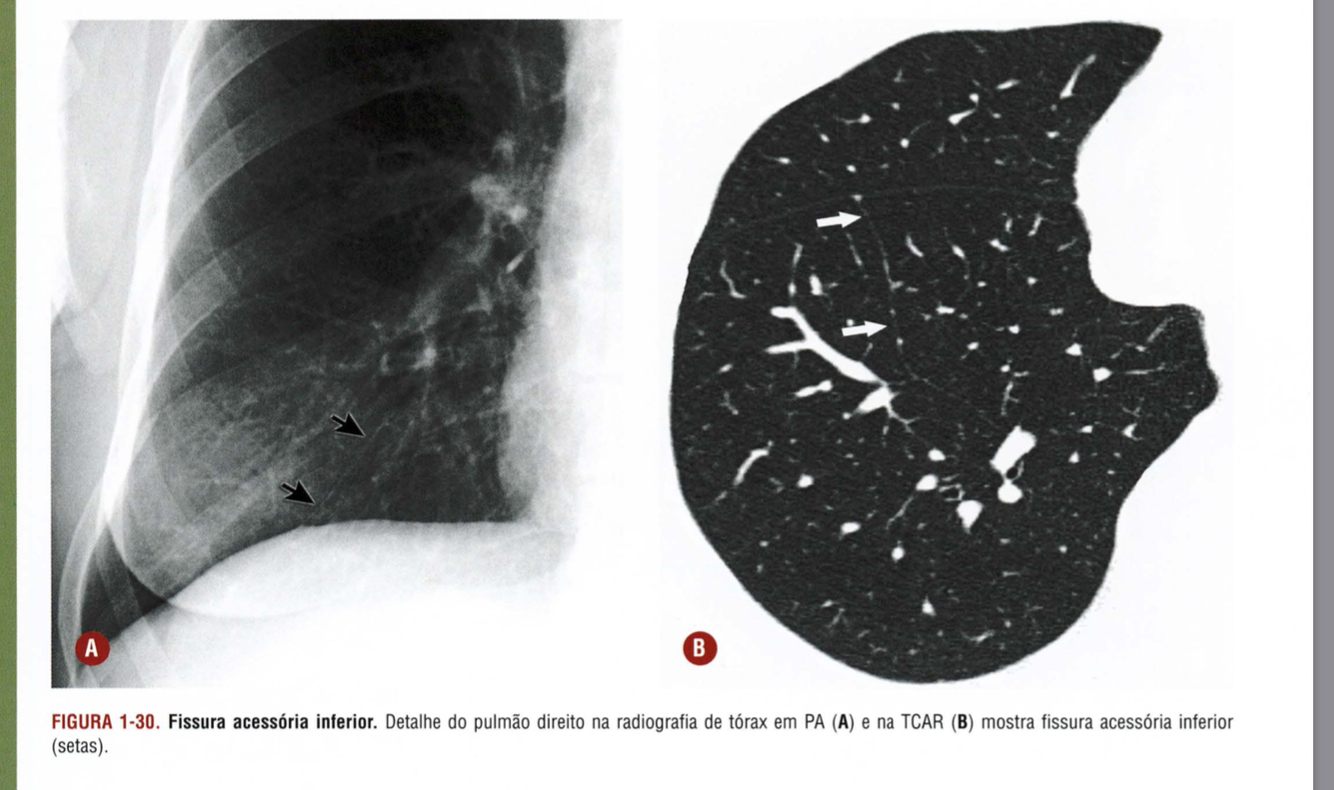

Qual a alteração demonstrada pelas setas?